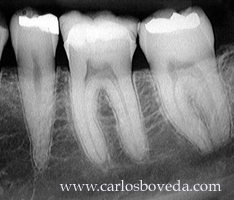

Video de un Tratamiento de Conductos en Una Sesión - (formato Quicktime)